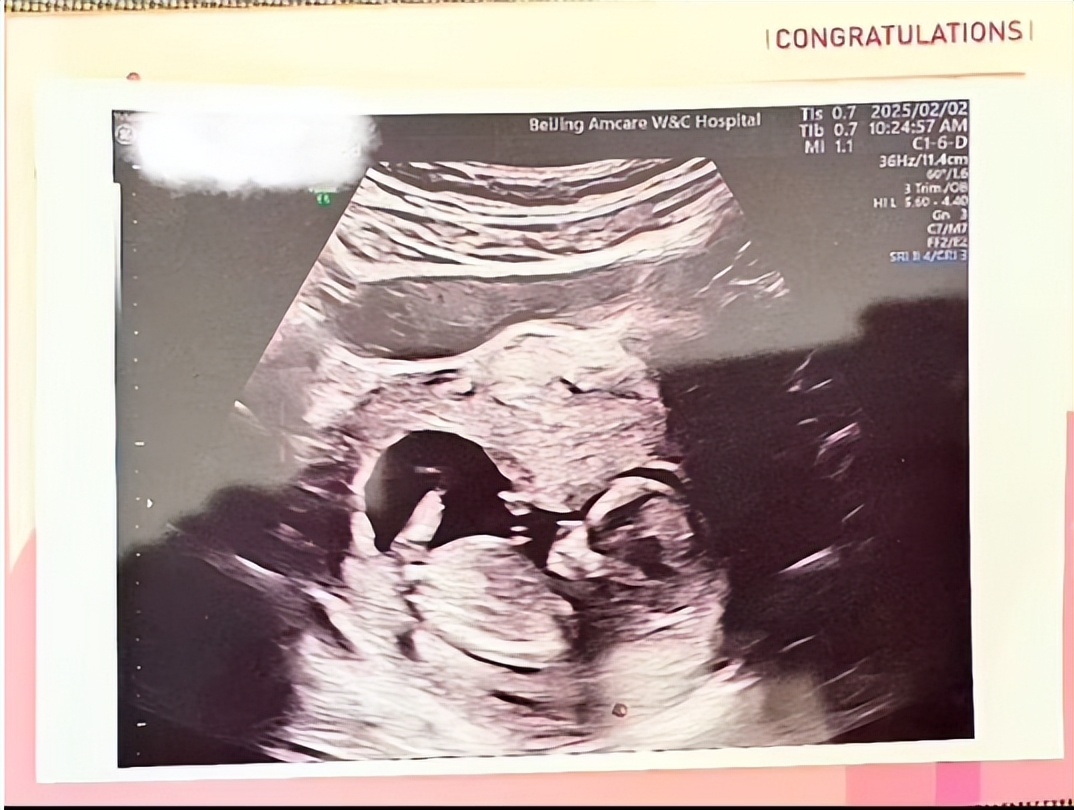

水亦诗开始时非常努力,后来因为要生孩子 ,工作就停了。她那时正在读研究生的最后一年,需要集中精力完成论文。宝宝第十二周的时候,她顺利地结束了孕吐期 ,还把超声波照片发给了大家 。宝宝满十四周,她写完了论文的初稿,不过后面还有很多格式要修改。